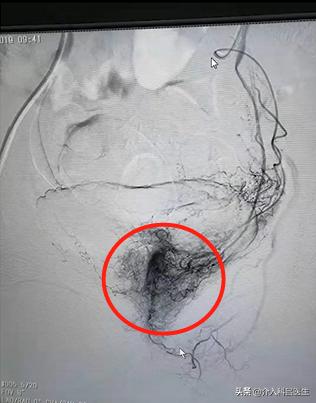

这样,因为 子宫内的环境没有改变,小的肌瘤得到了更多养分,就会长大,这就又复发了。赵女士复发之后,医院给的建议就是切除子宫,这样确实根治了,没有子宫了怎么长肌瘤?但是肯定是不舍得的,子宫不是阑尾说切就切了,这样重要的一个性器官,大多人是狠不下心去切除的。我们介入科,介入栓塞治疗的原理是什么?所有的肌瘤它连着两根血管,这两根血管给它栓塞,在这种情况下,不管子宫上有多少肌瘤,三五个也好,十个八个也好,所有的肌瘤都得不到营养。没有营养肌瘤就会“饿死了”,慢慢慢慢吸收掉。